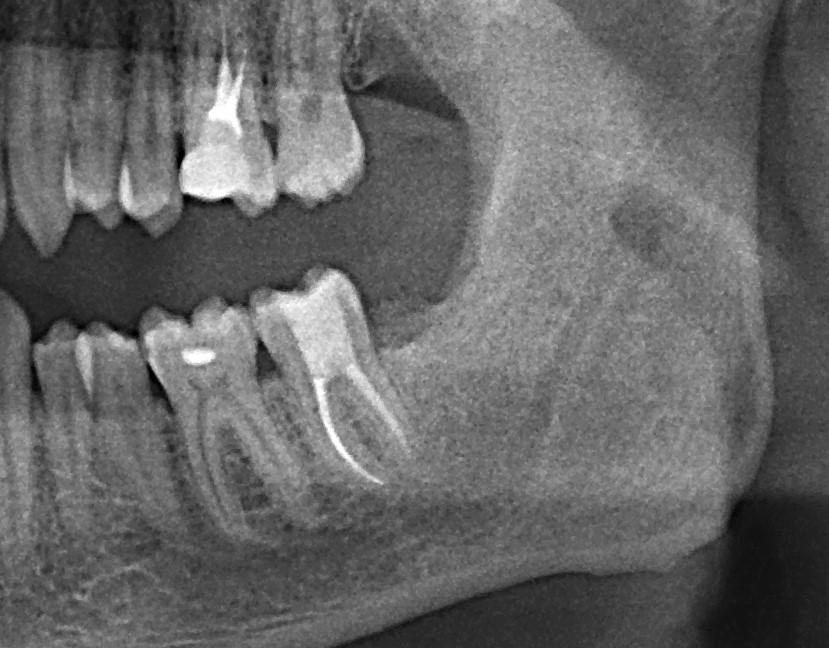

Обязательным обследованием для планирования операции синуслифтинга является компьютерная томография (КЛКТ). В верхнечелюстной пазухе могут быть перегородки и карманы, на обычном панорамном снимке увидеть их сложно. Также КЛКТ даёт возможность измерить расстояние АБ (с этого мы с вами начинали статью):